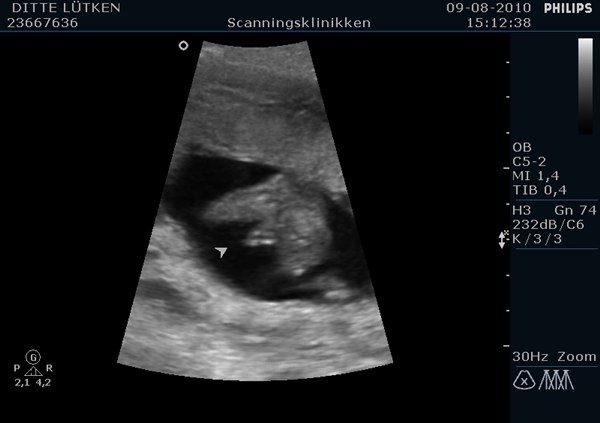

I får lige billeder af først tappen, man ser det nedefra mellem benene, og et andet billede hvor Bimmeren lige vinkede engang!